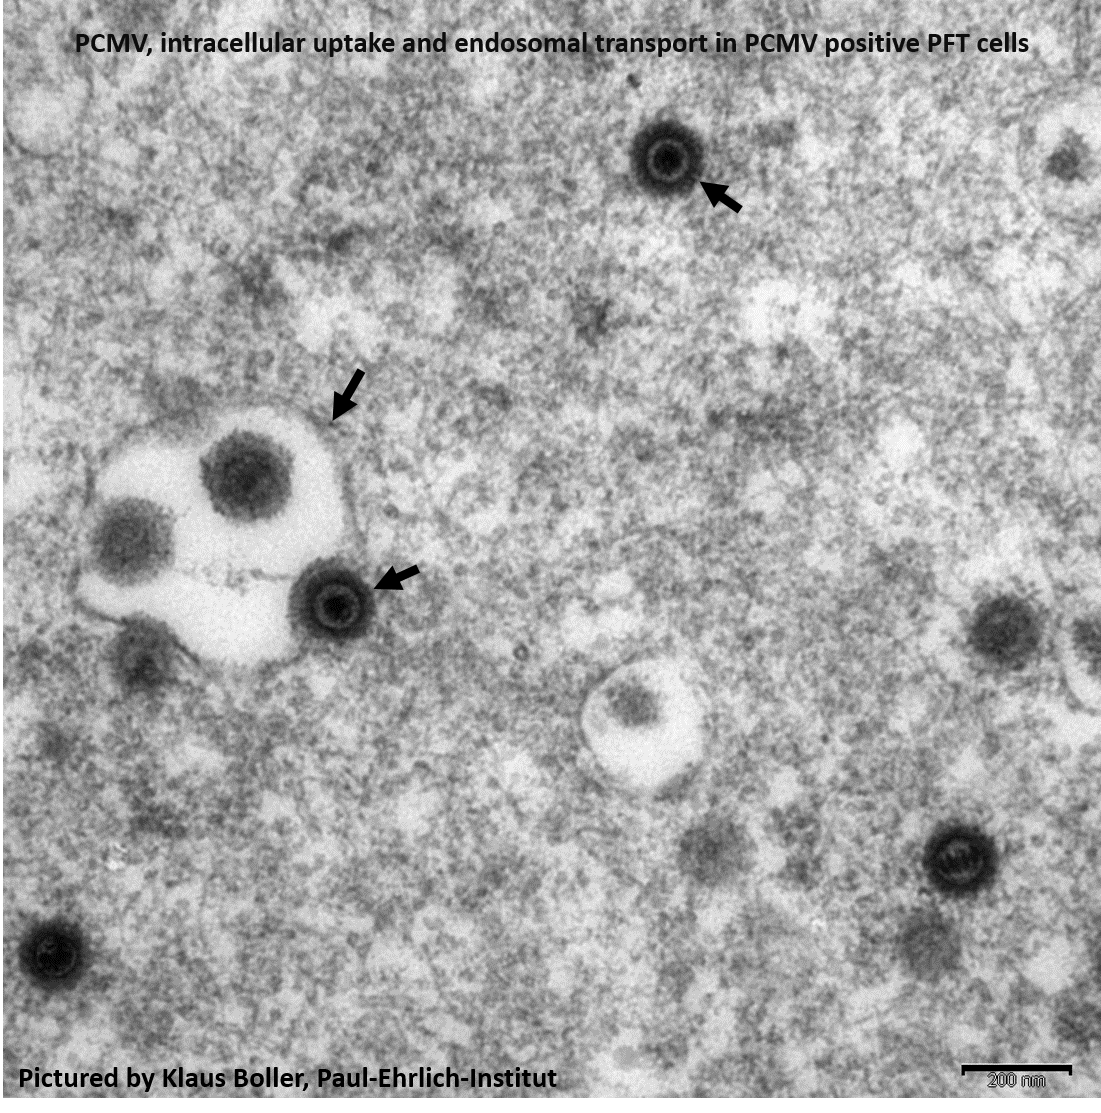

Method: Here, we report the development of five peptide-induced rabbit antisera specific for PCMV glycoprotein B (gB) and their validation for detection of PCMV in infected pig fallopian tube (PFT) cells by immunofluorescence and electron microscopy. The anti-gB antibodies were also used for detection by Western blot analysis of PCMV purified from the supernatant of infected PFT cells. Sera of infected vs. non-infected pigs have been compared. In parallel, PCMV viral load in blood samples of the animals was quantified by a novel highly sensitive nested-PCR and qPCR assay. A combination of four partly overlapping peptides from the gB C-terminus was used to establish a diagnostic ELISA for PCMV gB specific pig antibodies which is able to differentiate infected from non-infected animals and to quantify maternal antibodies in neonates.